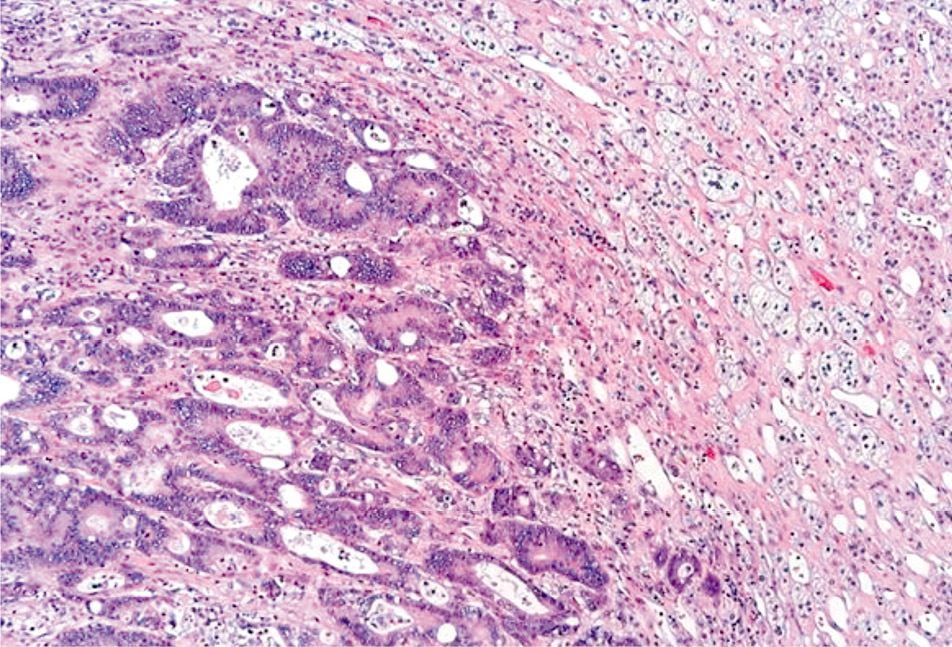

Компьютерная томография (КТ) грудной клетки, брюшной полости, забрюшинного пространства и таза 15.07.2022 (рис. 1): в левом надпочечнике опухолевидное образование неоднородной структуры размерами 71×73×72 мм, которое прилежит к хвосту поджелудочной железы на протяжении не менее 57 мм. Другой опухолевой патологии не выявлено. Заключение: КТ-картина опухолевого образования левого надпочечника.

Рис. 1. КТ грудной клетки, брюшной полости и забрюшинного пространства, таза с внутривенным контрастированием 15.07.2022.

Fig. 1. CT scan of the chest, abdomen and retroperitoneum, pelvis with intravenous contrast enhancement on July 15, 2022.